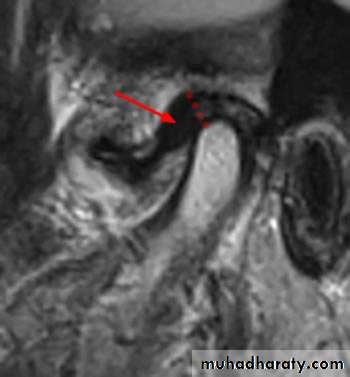

provides evaluation of a variety of hard and soft tissue pathology in the joint which can be done from a single radiation exposure. + CT images provide the most accurate radiographic assessment of the bony components of the joint• magnetic resonance imaging:

• which is most effective diagnostic imaging technique to evaluate TMJ soft tissue (intra-articular soft tissue) and for disk morphology and position with the fact that this technique does not use ionizing radiation is a significant advantagesDiseases of TMJ :A. traumatic arthritis:

• in this case movement of the condylar head is restricted and the damaged meniscus used to be blamed as the cause of the painful and locking joint. if the disk lies behind the condyle so it cannot return to its proper position in the glenoid fossa.